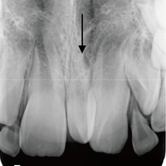

Quiste dentígero

Un quiste dentígero es un saco lleno de líquido que se forma alrededor de la corona de un diente no erupcionado.

Los pacientes pueden notar una hinchazón indolora en la mandíbula.

El tratamiento incluye la extirpación quirúrgica del quiste y, a veces, la extracción del diente involucrado.

Dientes Supernumerarios

Los dientes supernumerarios son dientes adicionales que pueden aparecer en la boca y causar problemas de alineación o erupción de otros dientes.

Los pacientes pueden notar dientes adicionales en la boca, lo que puede causar apiñamiento o problemas estéticos.

El tratamiento incluye la extracción quirúrgica de los dientes supernumerarios.